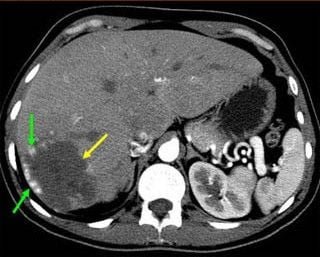

TC dinámica de un hemangioma pequeño en segmento II con alteración de la perfusión en fase arterial. Se cree que los shunts se abren por mecanismo transinusoidal.